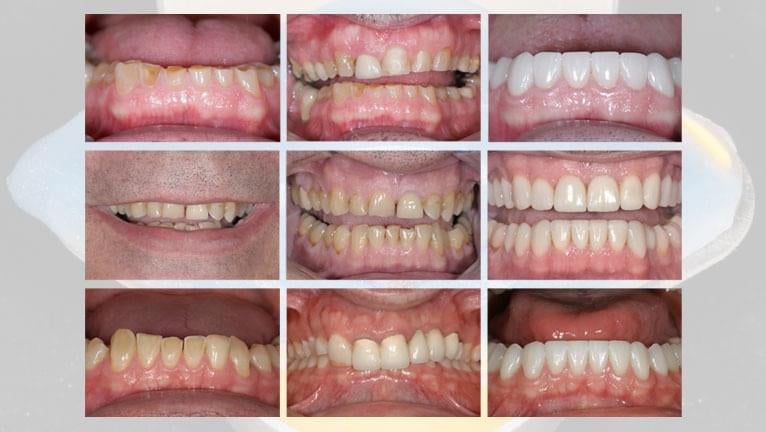

HOW TO RESTORE A PATIENT WITH SEVERE EROSION

This webinar will feature a detailed step-by-step case study for a patient with severe erosion treated with a partial rehabilitation by Dr. Stephen Phelan.

This webinar will teach you how to grow your dental practice by helping more of the moderate to severe tooth wear patients you’ve been avoiding.